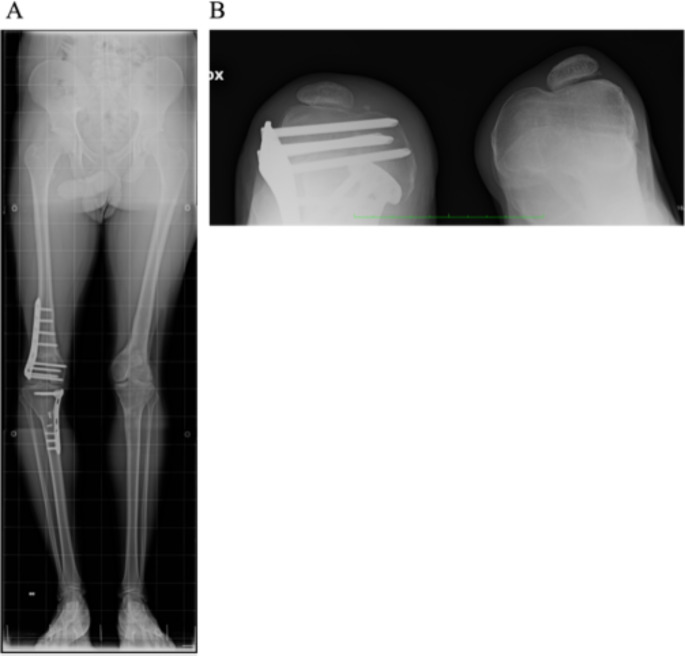

背景:先天性膝关节畸形是一种罕见疾病,其临床和遗传变异性很大,这主要是由于膝关节发育过程复杂。尽管在了解病理机制和相关基因方面取得了进展,但许多患者仍未得到诊断:揭示影响多个家庭成员且严重程度不一的先天性髌骨脱位的遗传基础:方法:我们对表现为双侧髌骨脱位的原发性髌骨脱位患者及其父亲、病情较轻的类似情况的姐姐以及未受影响的母亲进行了 ES 测序。然后,我们又对该患者的兄弟和姑姑进行了 Sanger 测序,他们也都受到了影响:ES 和 Sanger 测序结果表明,所有患病家庭成员的 TBX4 基因中都存在 c.735delT 的新型杂合换框突变。TBX4与常染色体显性的伴/不伴肺动脉高压(ICPPS,#147891)的等位-缺氧-足趾-髌骨综合征有关,并在该家族中得到确诊。家族内的临床异质性表明,可能还与其他因素有关,如 TBX4 或其他修饰基因的额外变异。有趣的是,我们只在表型更为严重的原告身上发现了 TBX4 基因的三个额外变异。尽管这些变异被归类为良性变异,但其中一个变异预计会破坏剪接蛋白的结合位点,因此可能会影响 TBX4 的替代剪接,从而导致该患者的表型更为严重:我们扩展并进一步划分了ICPPS的基因型和表型谱。结论:我们扩展并进一步划分了ICPPS的基因型和表型谱,有必要进一步研究该变异的潜在影响以及TBX4相关表型的不同表现。

Methods: We performed ES in the proband and his father, both showing bilateral patellar dislocation, his sister with a milder similar condition, and his unaffected mother. Sanger sequencing was then performed in the proband's brother and paternal aunt, both affected as well.

Results: ES and Sanger sequencing identified the presence of the novel heterozygous frameshift mutation c.735delT in the TBX4 gene in all affected family members. TBX4 is associated with autosomal dominant ischio-coxo-podo-patellar syndrome with/without pulmonary arterial hypertension (ICPPS, #147891), reaching a diagnosis in the family. Intrafamilial clinical heterogeneity suggests that other factors might be involved, such as additional variants in TBX4 or in other modifier genes. Interestingly, we identified three additional variants in the TBX4 gene in the proband only, whose phenotype is more severe. Despite being classified as benign, one of these variants is predicted to disrupt a splicing protein binding site, and may therefore affect TBX4 alternative splicing, accounting for the more severe phenotype of the proband.